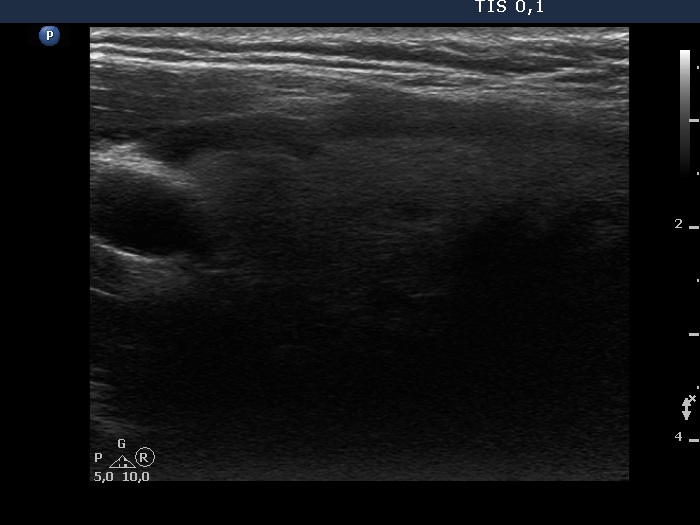

Teamwork - case 765 (ultrasonographic picture 6)

Left lobe, longitudinal scan.